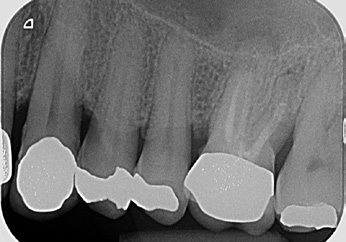

Ein 54-jähriger Patient wurde vom Hauszahnarzt mit der Bitte überwiesen, vor geplanter prothetischer Neuversorgung eine endodontische Revisionstherapie am Zahn 26 durchzuführen (Abb. 6). Der Zahn reagierte auf die Sensibilitätsprüfung mit CO2-Schnee negativ, auf Perkussion unauffällig. Die endodontische Diagnose lautete: Pulpastatus: pulpless and infected; periapikaler Status: asymptomatic apical periodontitis.

Mechanisch aufbereitet wurde mit den F360-Feilen im Endo- Pilot mobil bei 1,8 Ncm und 350 Upm (Abb. 8). Jedes Kanalsystem wurde anschließend chemisch mit CanalPro NaOCl und jeweils 3 x 30 Sekunden mit der Spülspitze SF65 schallaktiviert gereinigt. Die letzte aktivierte Spülsequenz wurde mit 17 % EDTA durchgeführt. Danach wurden die Kanalsysteme mit den zum System passenden Papierspitzen getrocknet. Die Obturation der Kanalsysteme wurde in einer Hybridtechnik mittels „continuous wave-technique“ (Downpack) und „Multi-Fill-Technik“ (Backfill) mit zum System passender Guttapercha und einem Sealer auf Epoxid-Polymer-Basis durchgeführt (Abb. 9).

Die temporäre koronale Restauration des Zahnes erfolgte mit einem dualhärtenden Komposit. Die röntgenologische Kontrolle zeigte eine dichte Versiegelung des kompletten Kanalsystems (Abb. 10). Der Patient wurde zur weiteren prothetischen Therapie an den Hauszahnarzt zurücküberwiesen.